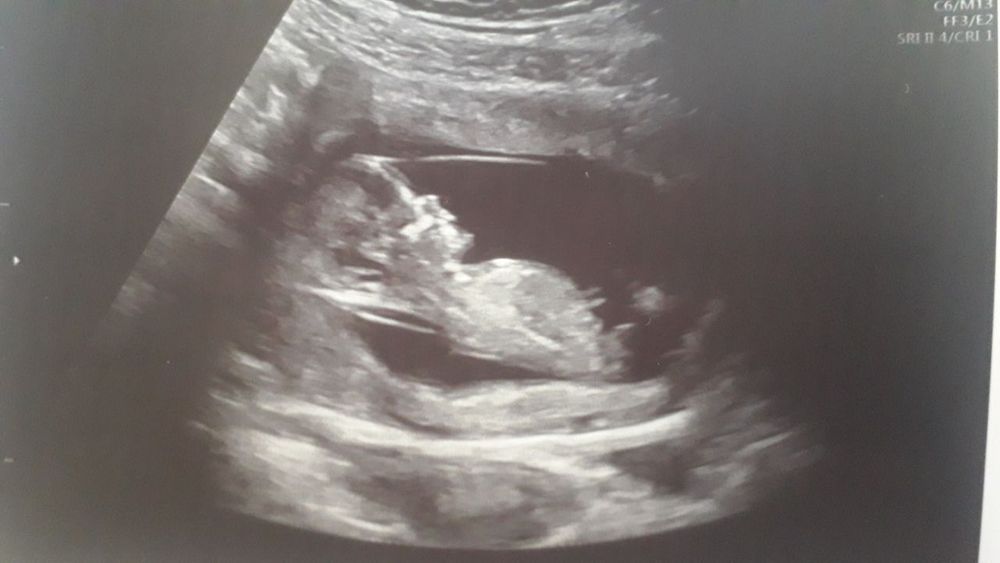

Первый скрининг ))) фото малявки

Наши будни, наши неделькиСходила на скрининг! Все у нас хорошо))) хочу поскорее домой, чтоб там спокойно поплакать от счастья. У меня сегодня 12.3, на узи намерили 13.2 уже! Все в норме, малыш дрыгается там)))